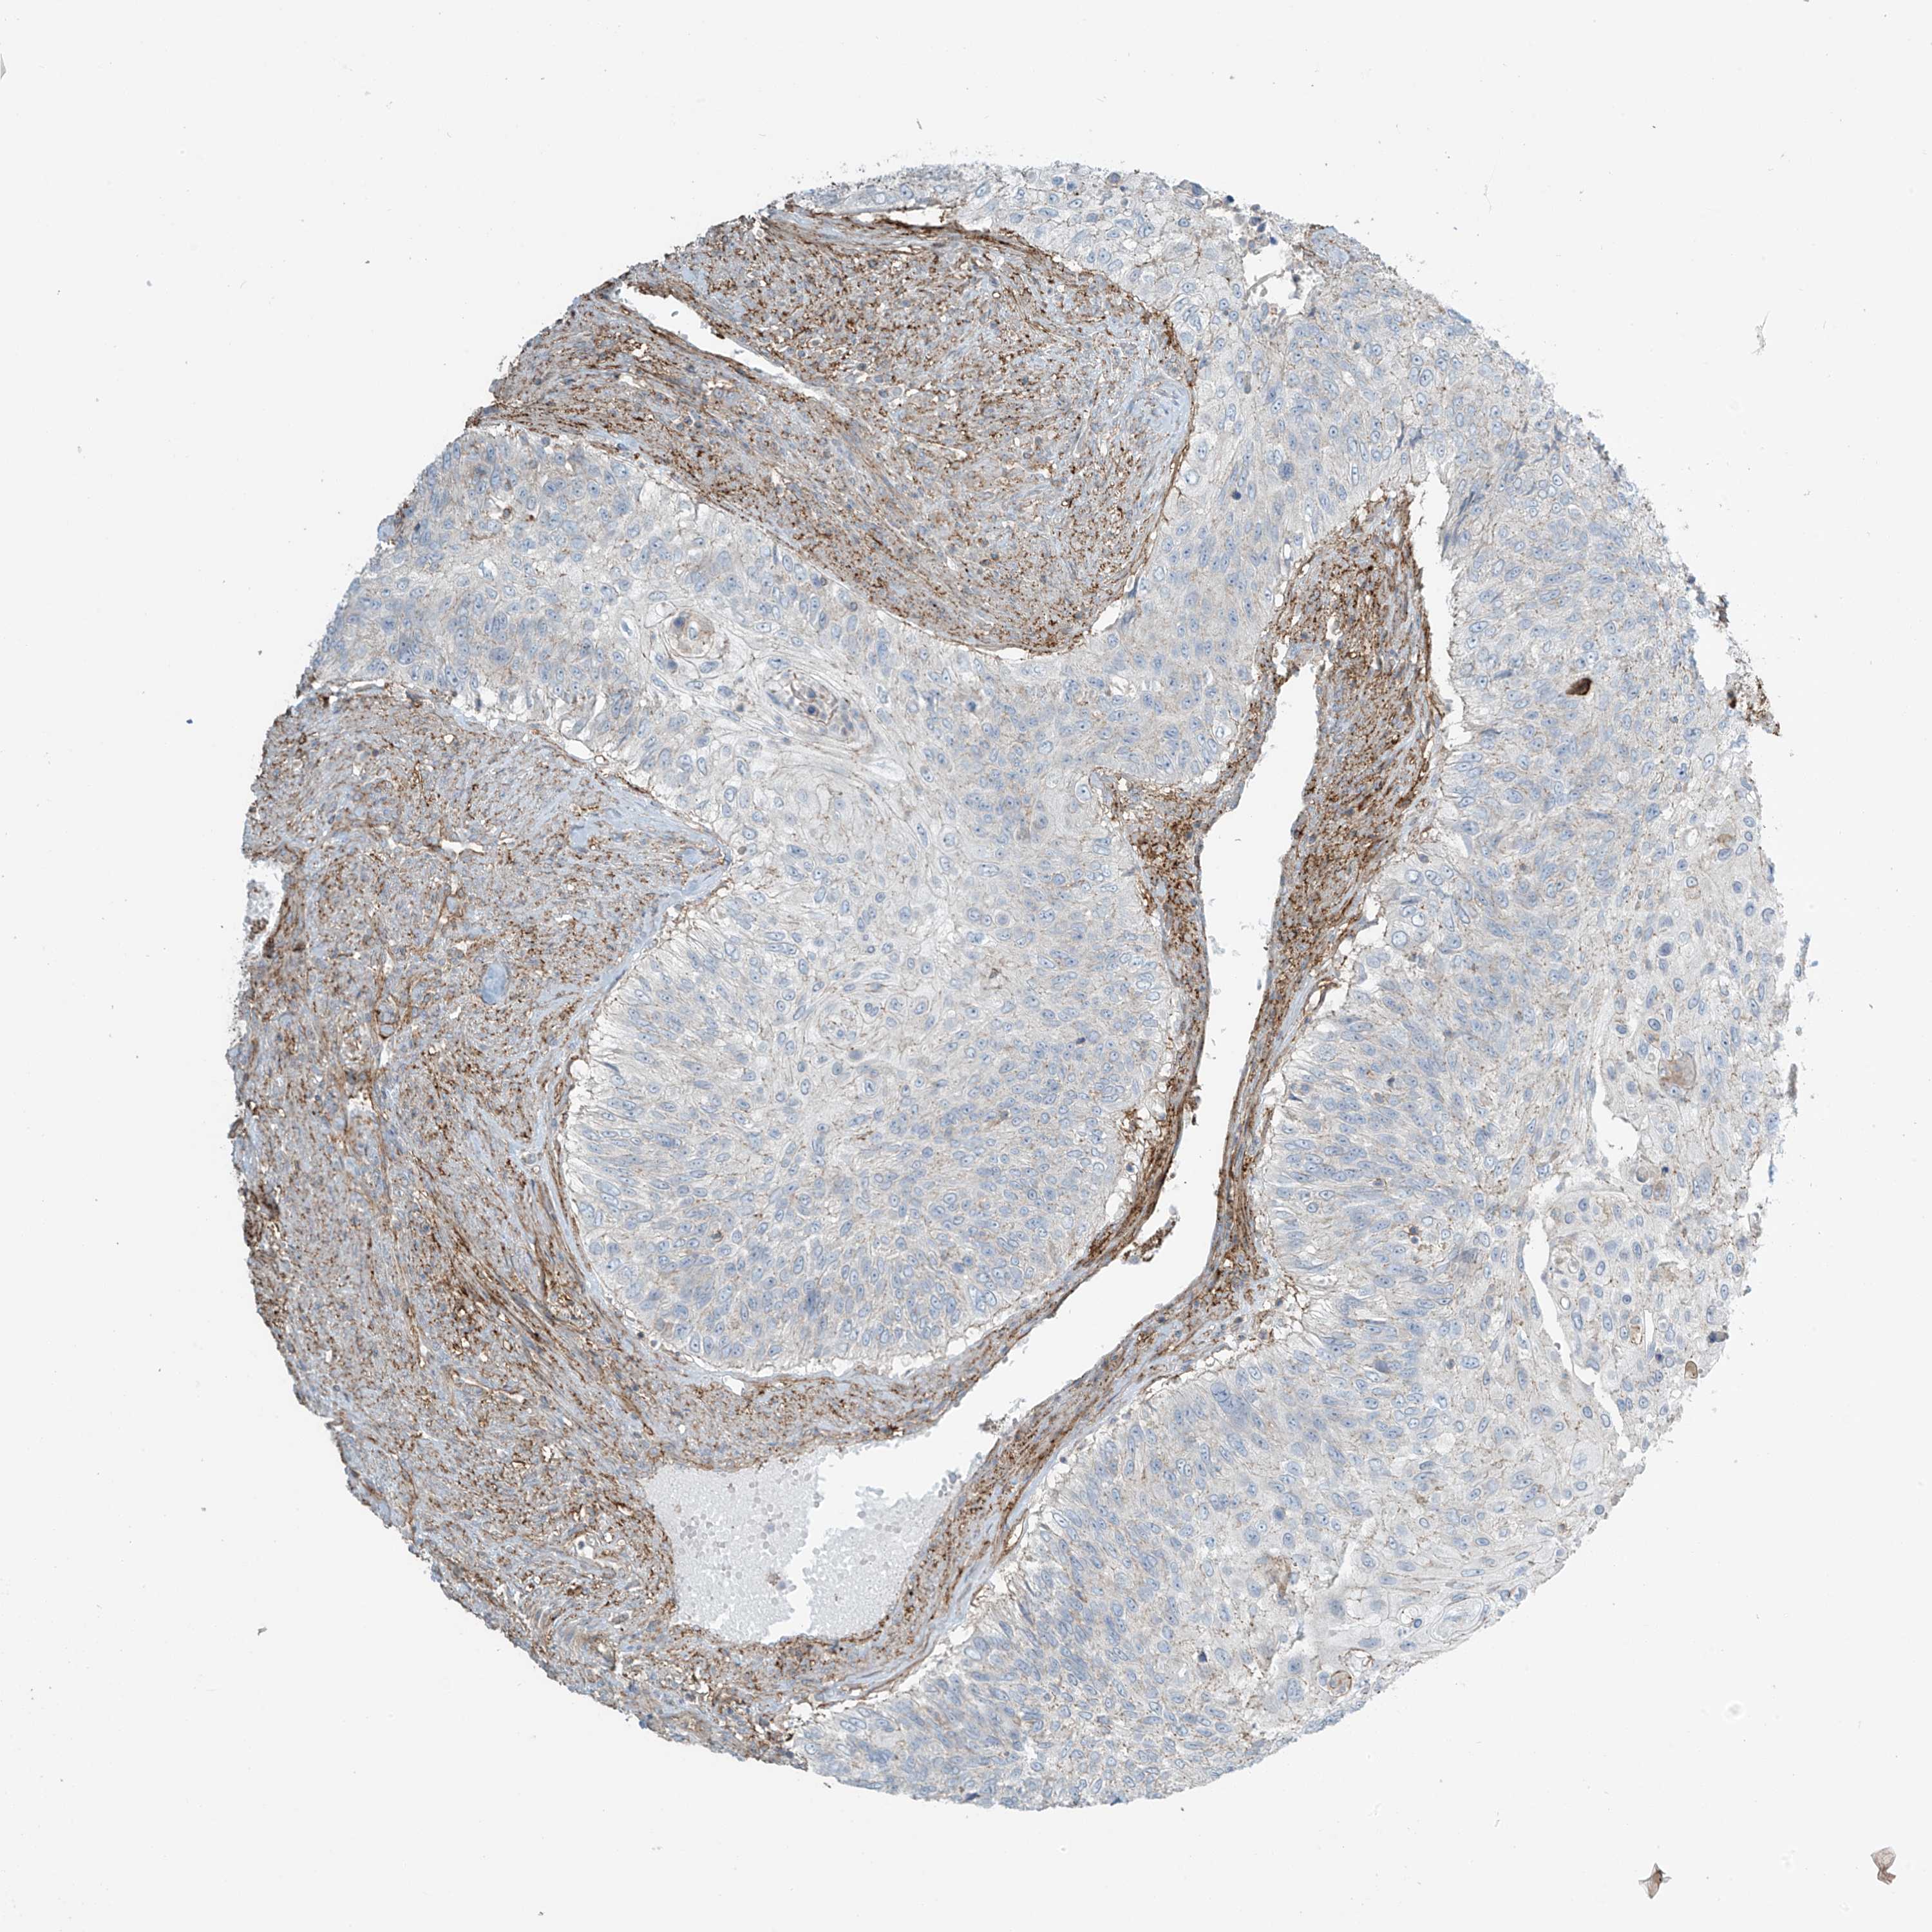

UROTHELIAL CANCER - Protein expressioni

A mouse-over function shows sample information and annotation data. Click on an image to view it in a full screen mode. Samples can be filtered based on level of antibody staining by selecting one or several of the following categories: high, medium, low and not detected. The assay and annotation is described here.

Note that samples used for immunohistochemistry by the Human Protein Atlas do not correspond to samples in the TCGA dataset.

Antibody stainingi

Antibody staining in the annotated cell types in the current human tissue is reported as not detected, low, medium, or high, based on conventional immunohistochemistry profiling in selected tissues. This score is based on the combination of the staining intensity and fraction of stained cells.

Each image is clickable and will lead to virtual microscopy that enables deeper exploration of all samples and also displays staining intensity scores, fraction scores and subcellular localization as well as patient and tissue information for each sample.

Antibody HPA035121

Antibody HPA035122

Staining

High

Medium

Low

Not detected

Intensity

Strong

Moderate

Weak

Negative

Quantity

>75%

75%-25%

<25%

None

Location

Nuclear

Cytoplasmic/membranous

Cytoplasmic/membranous,nuclear

Urothelial carcinoma, High grade

Urothelial carcinoma, Low grade